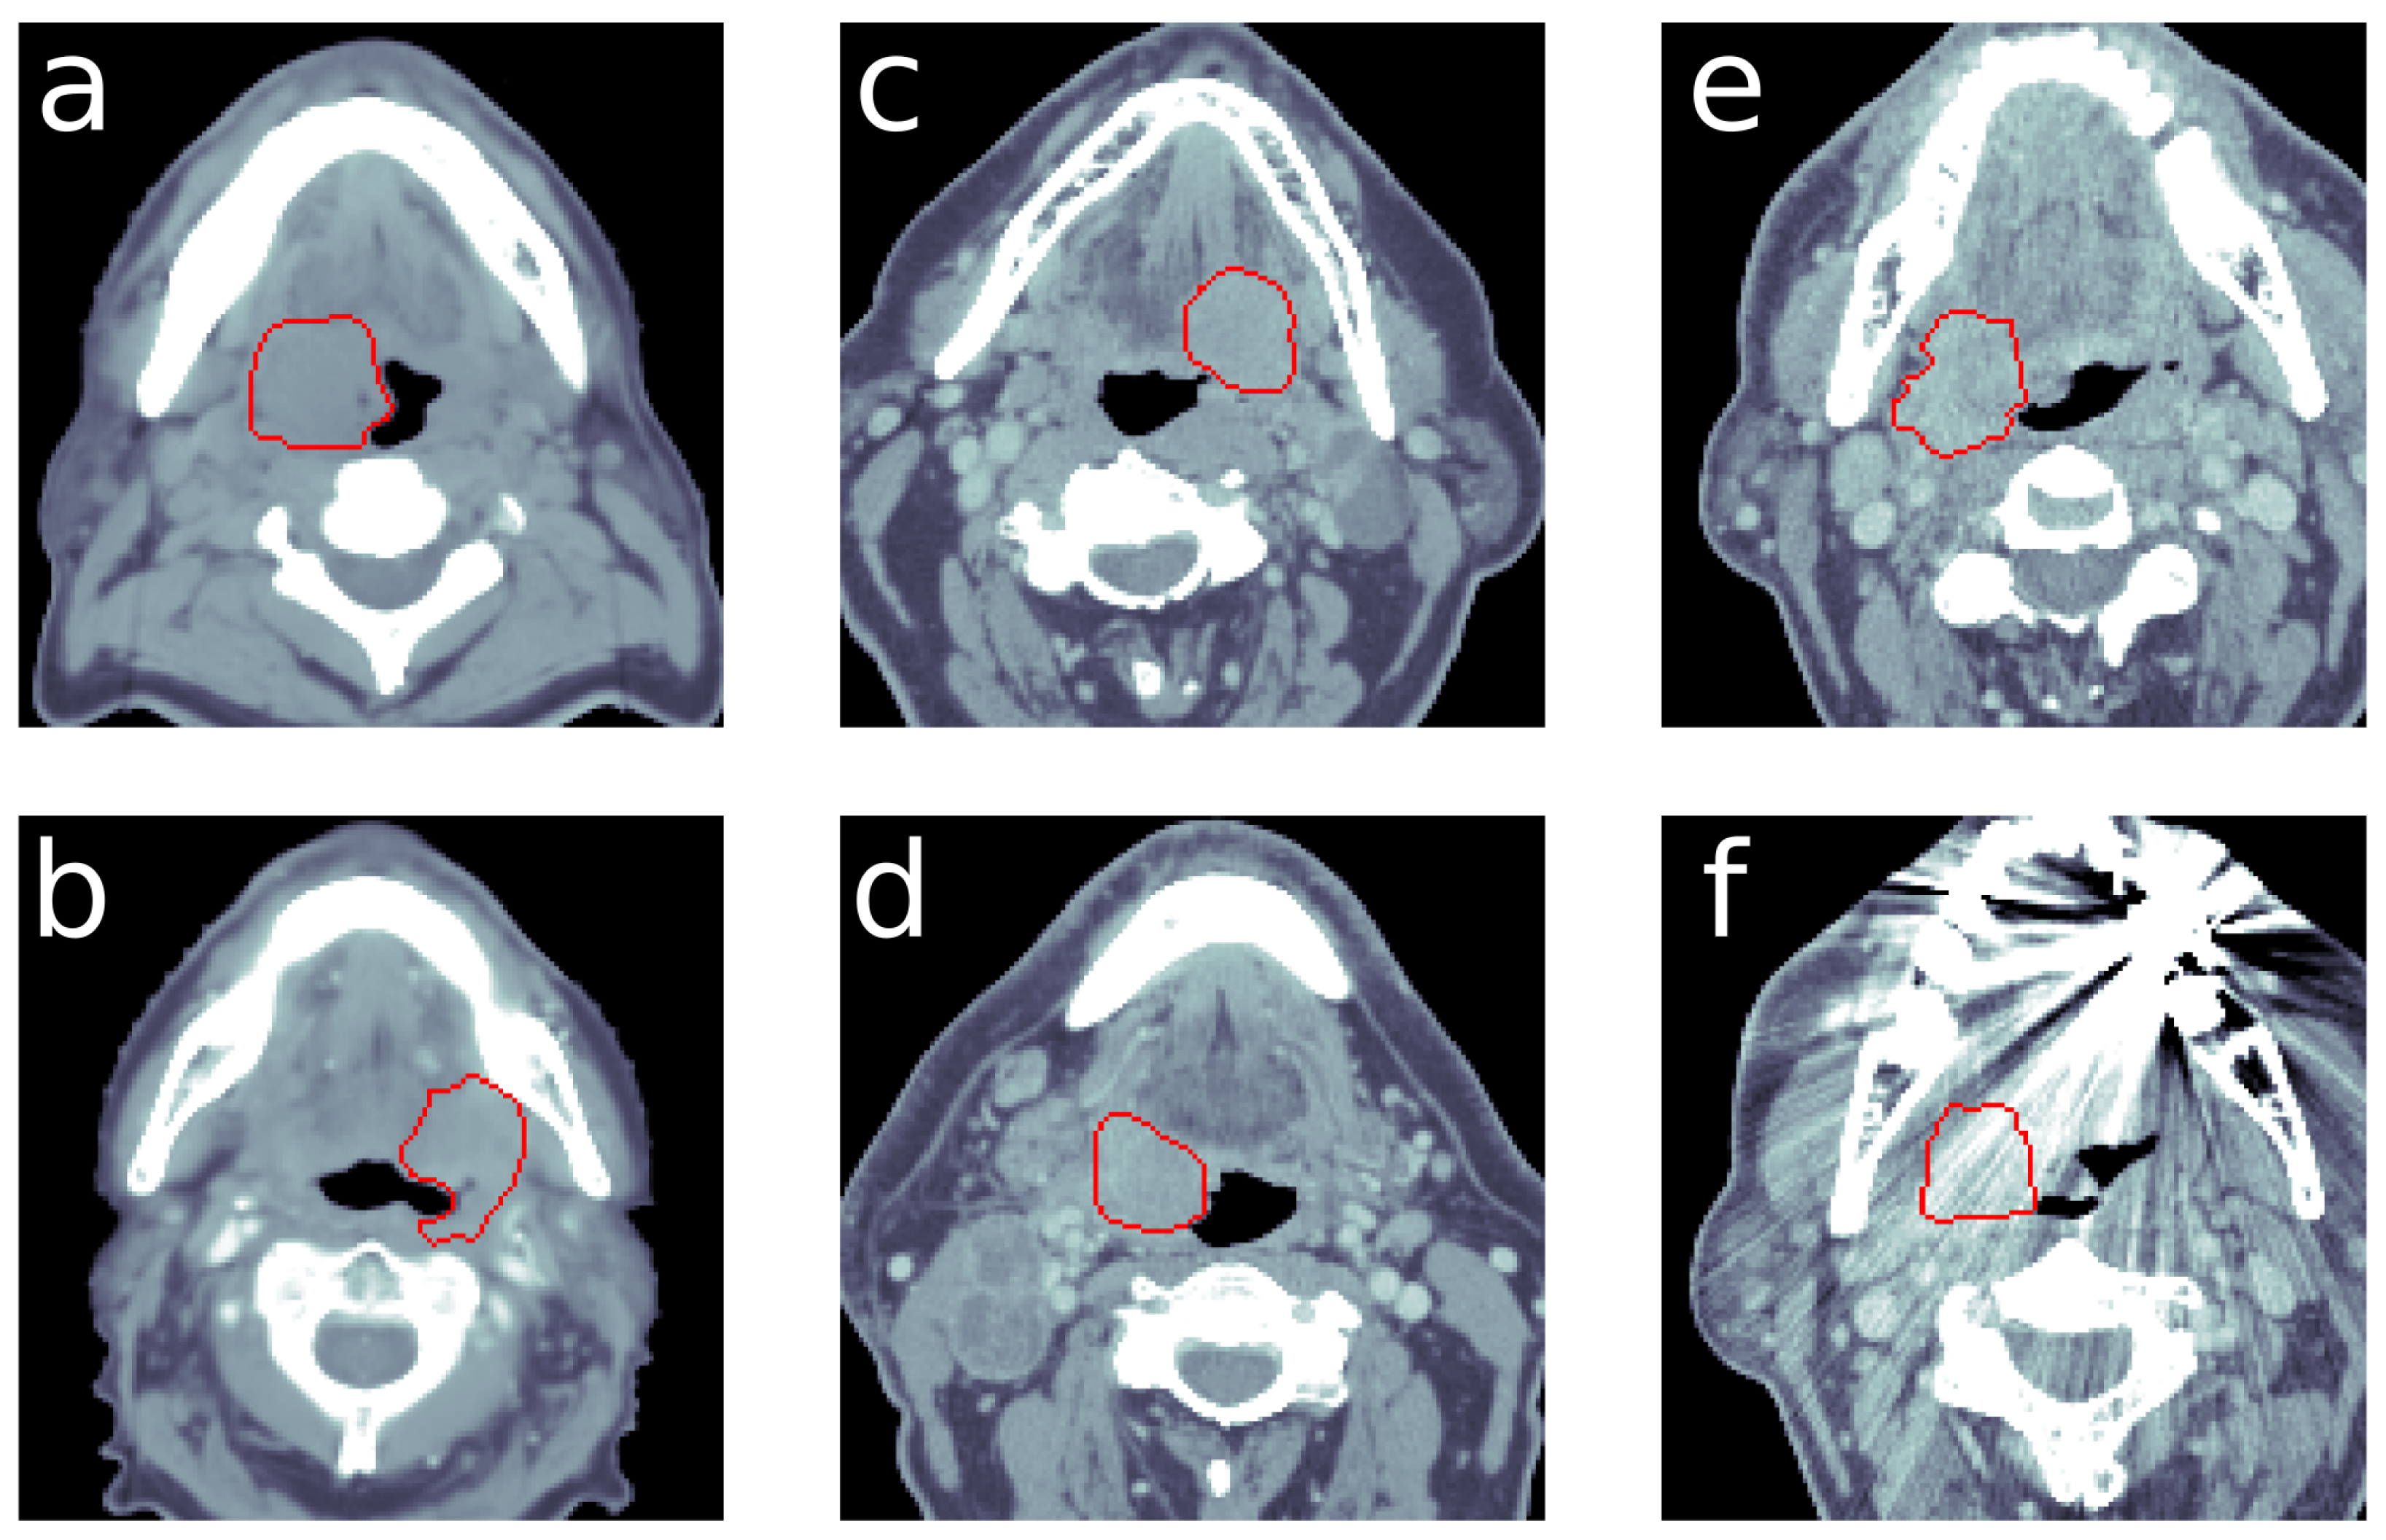

Example CT slices with: (a) HPV-positive example (OPC dataset), (b) HPV-negative example (OPC dataset), (c) HPV-positive example (HNSCC dataset) and (d) HPV-negative example (HNSCC dataset). Examples (e,f) are showing different slices of the same CT image, while (e) features normal quality (f), which suffers from artifacts. The red delineation marks the gross tumor volume. The HU window was set to range from −250 to 250.

Additionally, we recognize improved performance of the 3D approach over the 2D approach. Our results suggest that the third dimension contains essential information for HPV classification. Since the 2D case uses only small parts of the complete CT image, a 3-dimensional input volume enables a better fit to the data. The small input volume increases the probability to receive slices that lack information on patient’s HPV status and impair the training progress. Moreover, single slices can suffer from artifacts, of which Figure A2 gives an impression. Providing only three CT slices increases the impact of such artifacts and compromises training success.